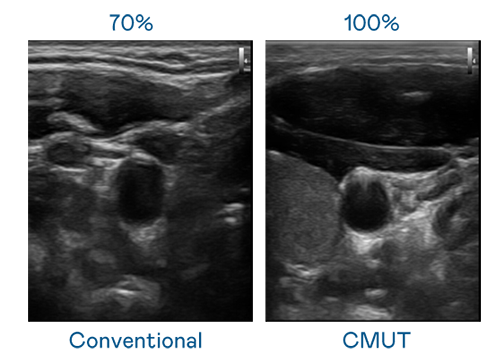

CMUT 技术是一种用电容式微机电元件来产生超音波讯号的技术。与传统 PZT 压电式技术相比,CMUT 频宽增加 30%,更宽频的超音波讯号让影像解析度大幅提升,是实现高影像品质医疗超音波扫描、促进精准医疗发展的关键技术。

大频宽带来超清晰影像

超音波影像的解析度高低,首先取决于探头能发出的讯号频宽。彩霸王官网 CMUT 可提供高清晰的超音波讯号,提供高频宽、高灵敏度、影像纹理细节更高的超音波影像,协助医护人员缩短影像判读时间及利用精准的医疗影像进行诊断。